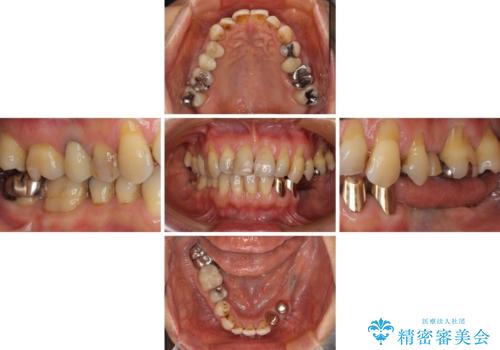

- 義歯を使いたくないものの、骨の幅が狭くインプラント治療を断られているとのことで来院された患者様です。

レントゲンやCTより、骨の高さと幅が不足しており、骨を増やす必要のある状態でした。

しかしながら、全身疾患により骨造成術の予後に不安があったため、デンサーバー(Densah ® Bur)という骨幅を増大することが可能なドリルを用いてインプラントを埋入することとしました。

入れ歯の支台となっていたコーヌスのゴールドも除去し、インプラント部と合わせてオールセラミッククラウンにて補綴治療を行うこととしました。